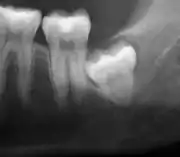

Impacted wisdom teeth are classified by their direction of impaction, their depth compared to the biting surface of adjacent teeth and the amount of the tooth's crown that extends through gum tissue or bone. Impacted wisdom teeth can also be classified by the presence or absence of symptoms and disease. Screening for the presence of wisdom teeth often begins in late adolescence when a partially developed tooth may become impacted. Screening commonly includes a clinical examination as well as x-rays such as panoramic radiographs.

Impacted wisdom teeth are classified by the direction and depth of impaction, the amount of available space for tooth eruption, and the amount of soft tissue or bone (or both) that covers them. The classification structure helps clinicians estimate the risks for impaction, infections and complications associated with wisdom teeth removal.[6] Wisdom teeth are also classified by the presence (or absence) of symptoms and disease.[7]

One review found that 11% of wisdom teeth will have evidence of disease and are symptomatic, 0.6% will be symptomatic but have no disease, 51% will be asymptomatic but have disease present and 37% will be asymptomatic and have no disease.[7] Impacted wisdom teeth are often described by the direction of their impaction (forward tilting, or mesioangular being the most common), the depth of impaction and the age of the patient as well as other factors such as pre-existing infection or the presence of pathology (cysts, tumors or other disease).[5]: 143–144 Each of these factors is used to predict the difficulty (and rate of complications) when removing an impacted tooth, with age being the most reliable predictor[8] rather than the orientation of the impaction.[9]